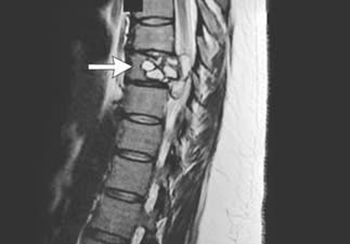

A few years ago, a woman in her mid-20s suddenly found herself unable to walk. She'd stand up, only for her muscles to give out and drop her to the floor. She was also doubled over in pain, suffering an electric sensation running through her back. She eventually visited her local hospital, and one MRI later, she had a diagnosis. Her spine was infected with tapeworm larvae.

As far as anyone call tell, the patient (somehow) accidentally ingested the egg of a tapeworm species that usually only infects dogs and farmyard animals, whereupon it rode her bloodstream like a red river rapids ride until it eventually lodged in her vertebrae. There, the egg hatched and developed into a cyst. The muscular weakness? The electrical shocks? Those were all caused by the cyst and its tapeworm occupants bumping and wiggling and hacking their way to her central nervous system, which ran clear through that vertebrae.